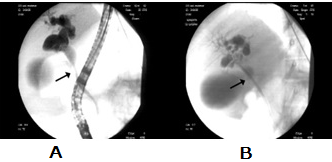

Figure 4: ERCP images. 4A: There is a stricture in the distal CHD and dilatation in the proximal CHD. 4B: ERCP image obtained after CBD stent placement.

figure 4